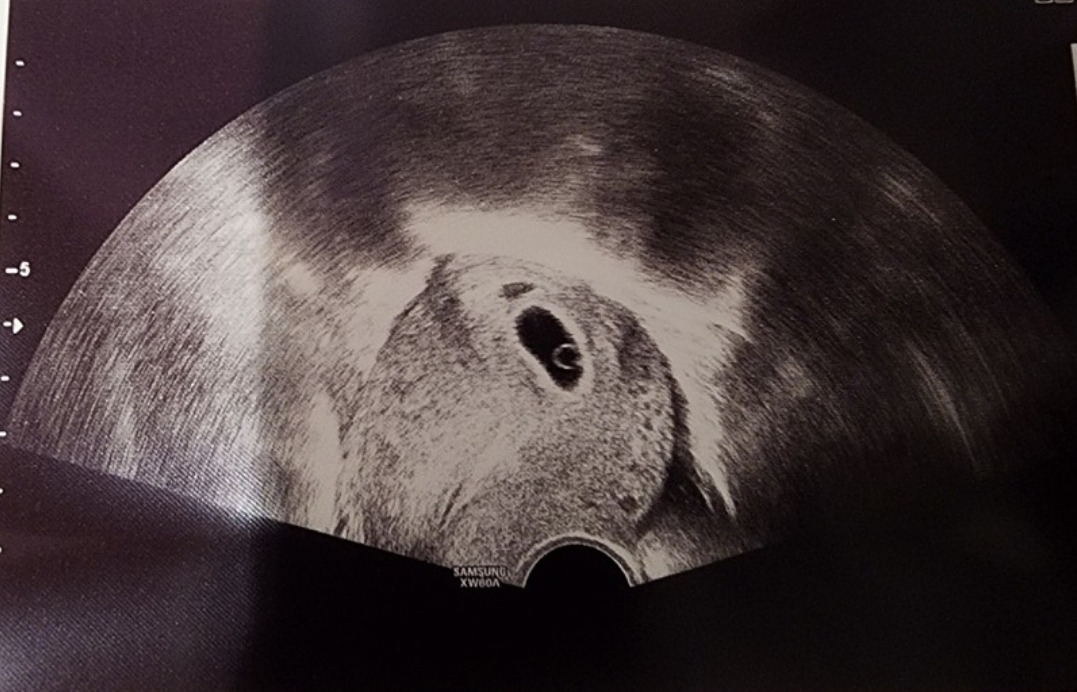

사실 지금도 네가 나에게 왔다는 게 실감이 나지 않아. 처음 피검사를 해서 너라는 존재가 있다는 것을 인지하게 되었을 때에도 얼떨떨했어. 믿기지 않아서, 또 실망하게 되는 게 싫어서 너의 이름조차도 만들지 못했어. 그리고 두 번째 피검사에서 너는 너의 존재감을 드러냈어. 증가해 가는 hCG 수치를 보니 정말로 네가 나의 자궁벽에 착상을 해서 조금씩 조금씩 파고들고 있었어.

5주가 되기 전까지 너의 존재를 확인하는 방법은 임신테스트기의 두 줄, 그리고 병원에서 피검사로 hCG 수치를 보는 두 가지 방법뿐이었단다. 피검사를 하면서 양팔에 주삿바늘의 멍이 들었어도 기쁘기만 했어. 2차 피검사로 널 확실히 안 날에는 너의 이모에게 한껏 자랑했어.

아직 너를 내 눈으로 보기 전까지는 이렇게 글을 쓰고 있는 나도 믿기지 않거든.